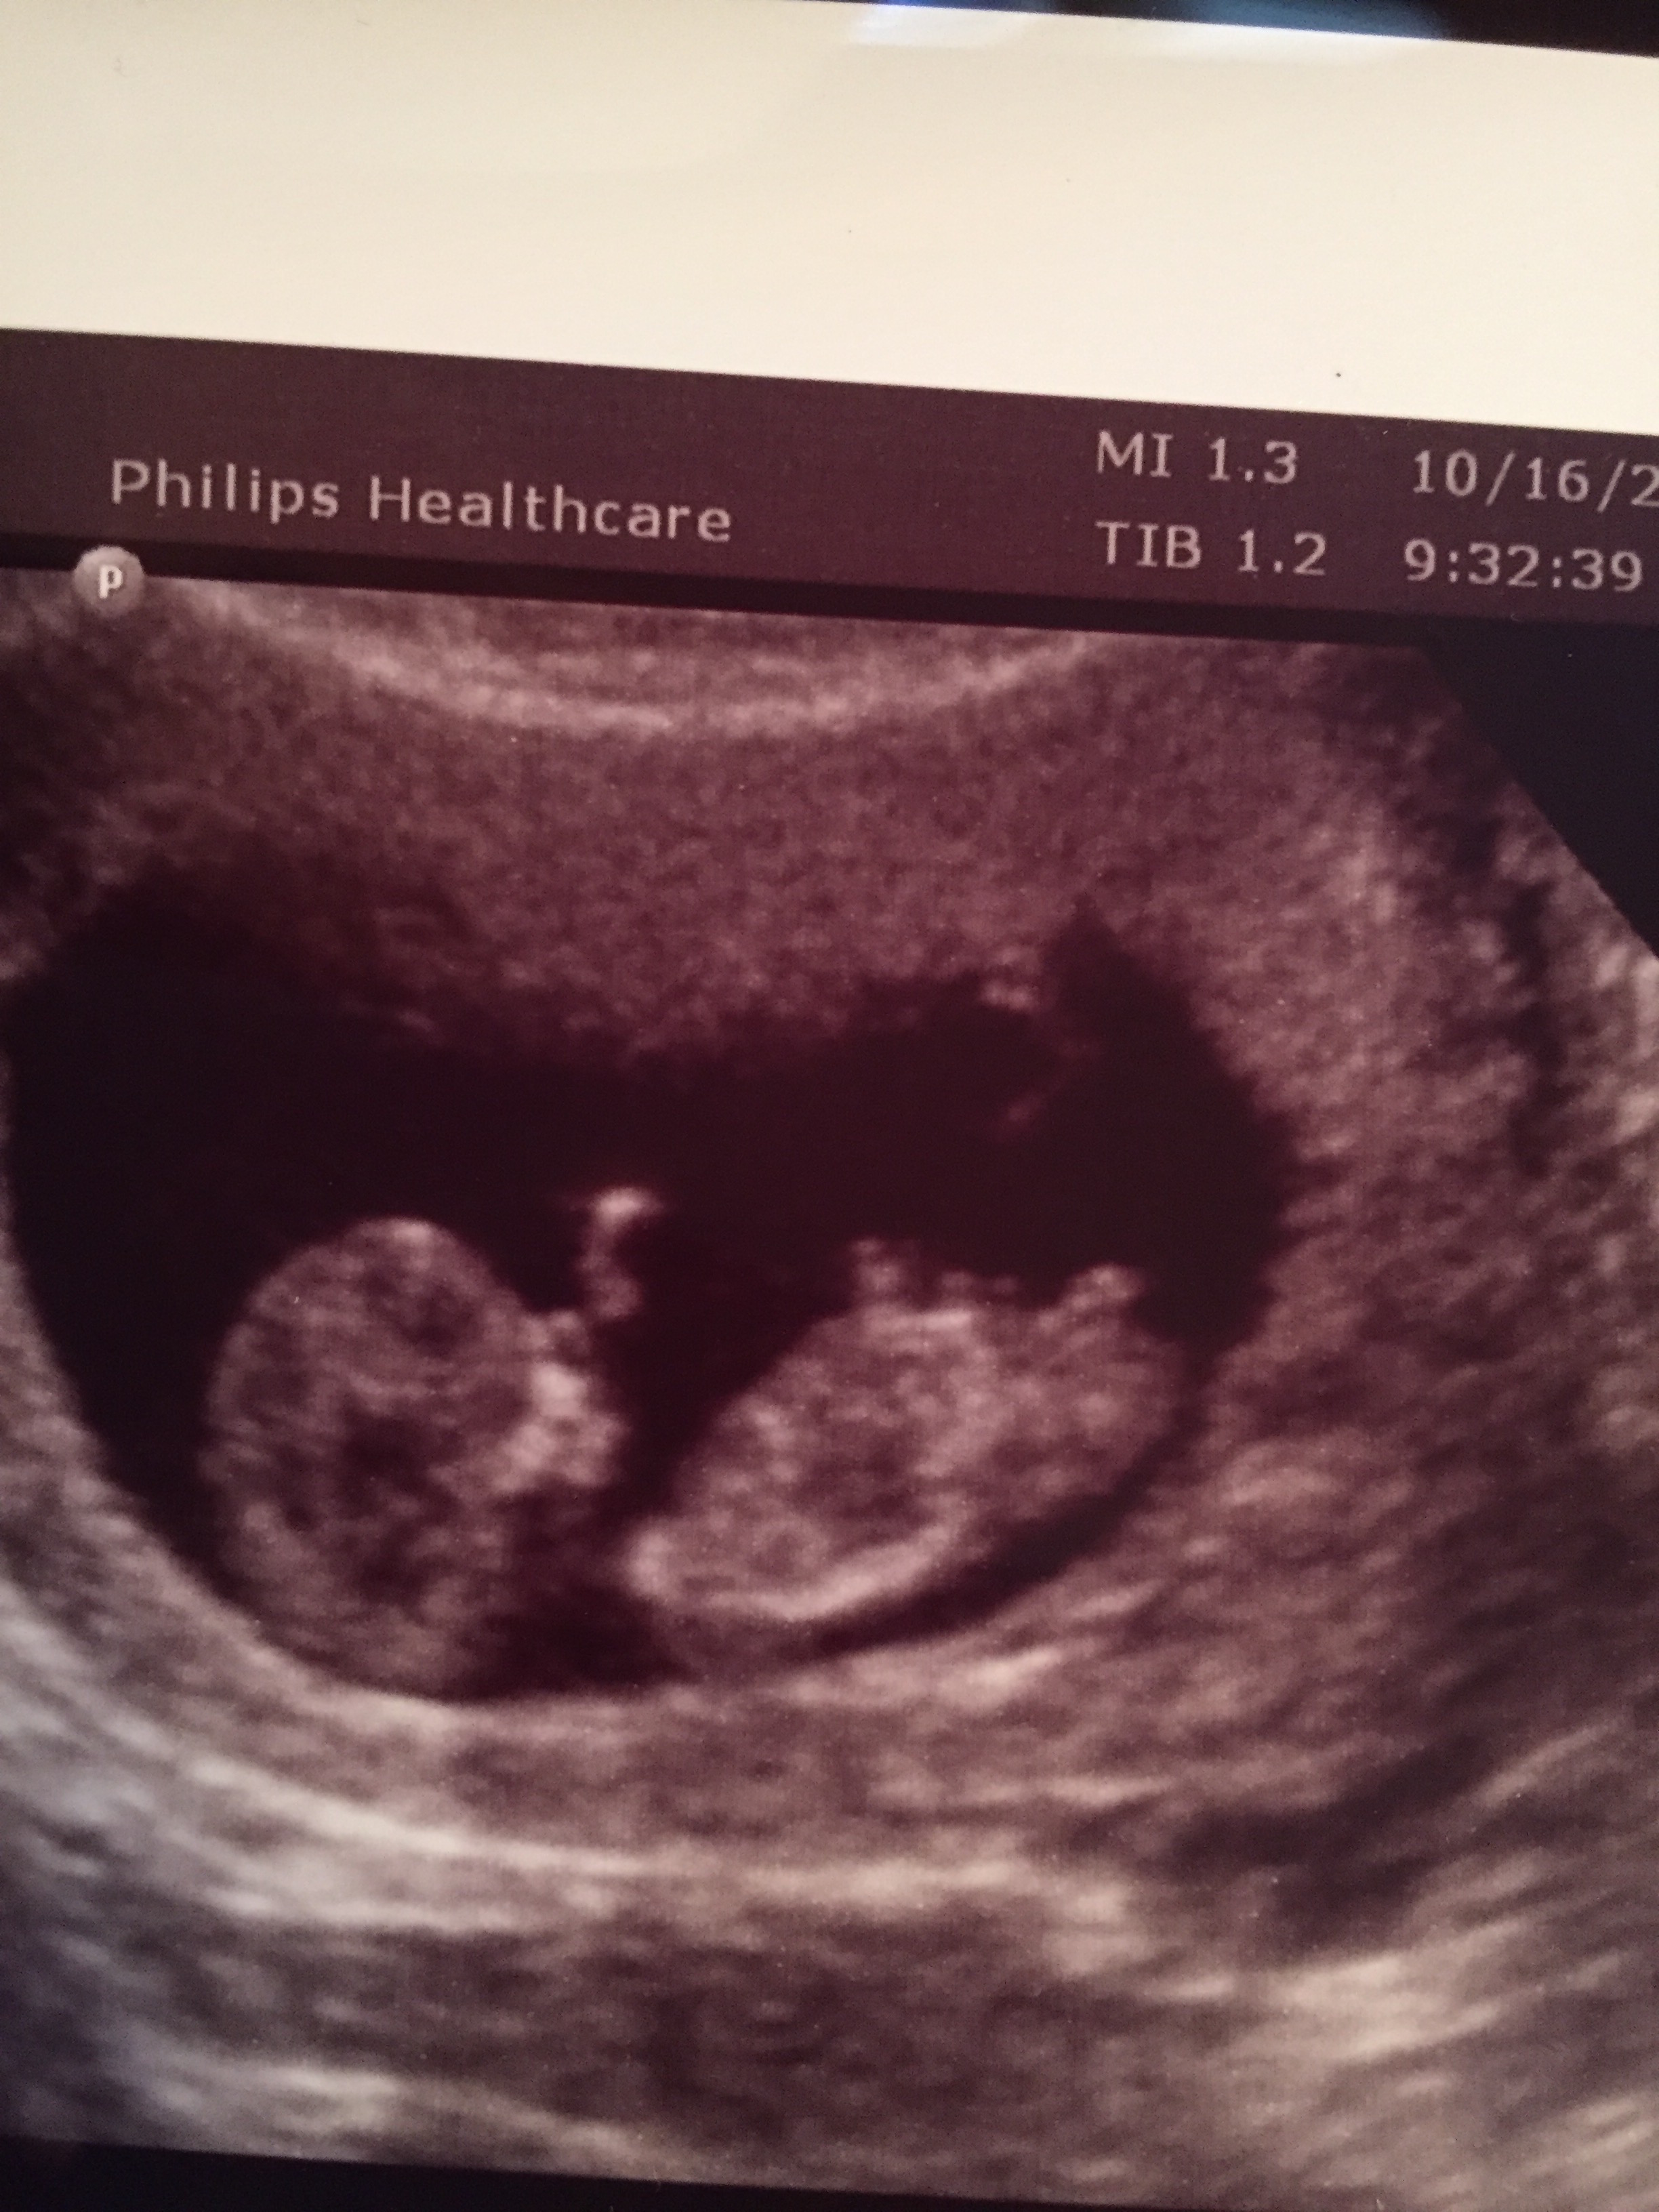

Attachment 28376Someone told me this is a boy nub. I previously posted two pics on here and got all boy guesses from other photos but someone said by looking at this picture from my sonogram( I didn't post this picture since I didn't feel like I could see anything) that the circle area is a boy nub. Any insight would be appreciated.Gender scan is on friday so any last guesses? Thanks so much ladies!!!Attachment 28374